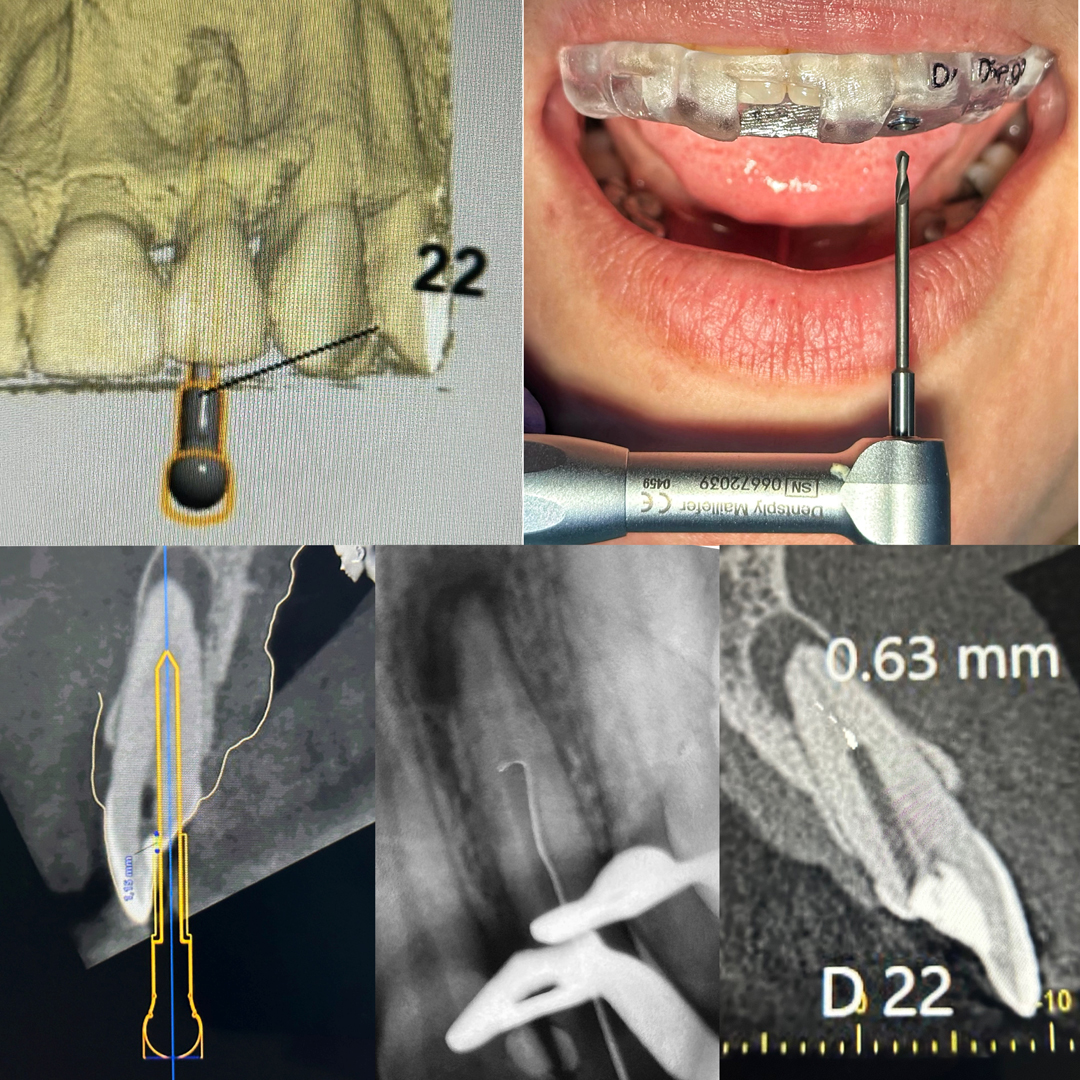

● Endodontia guiada (endoguide)

● Resolução de casos complexos

Tratamento de canal com foco em preservação do dente, controle da infecção e eliminação da dor.

● Tratamento e retratamento de canal